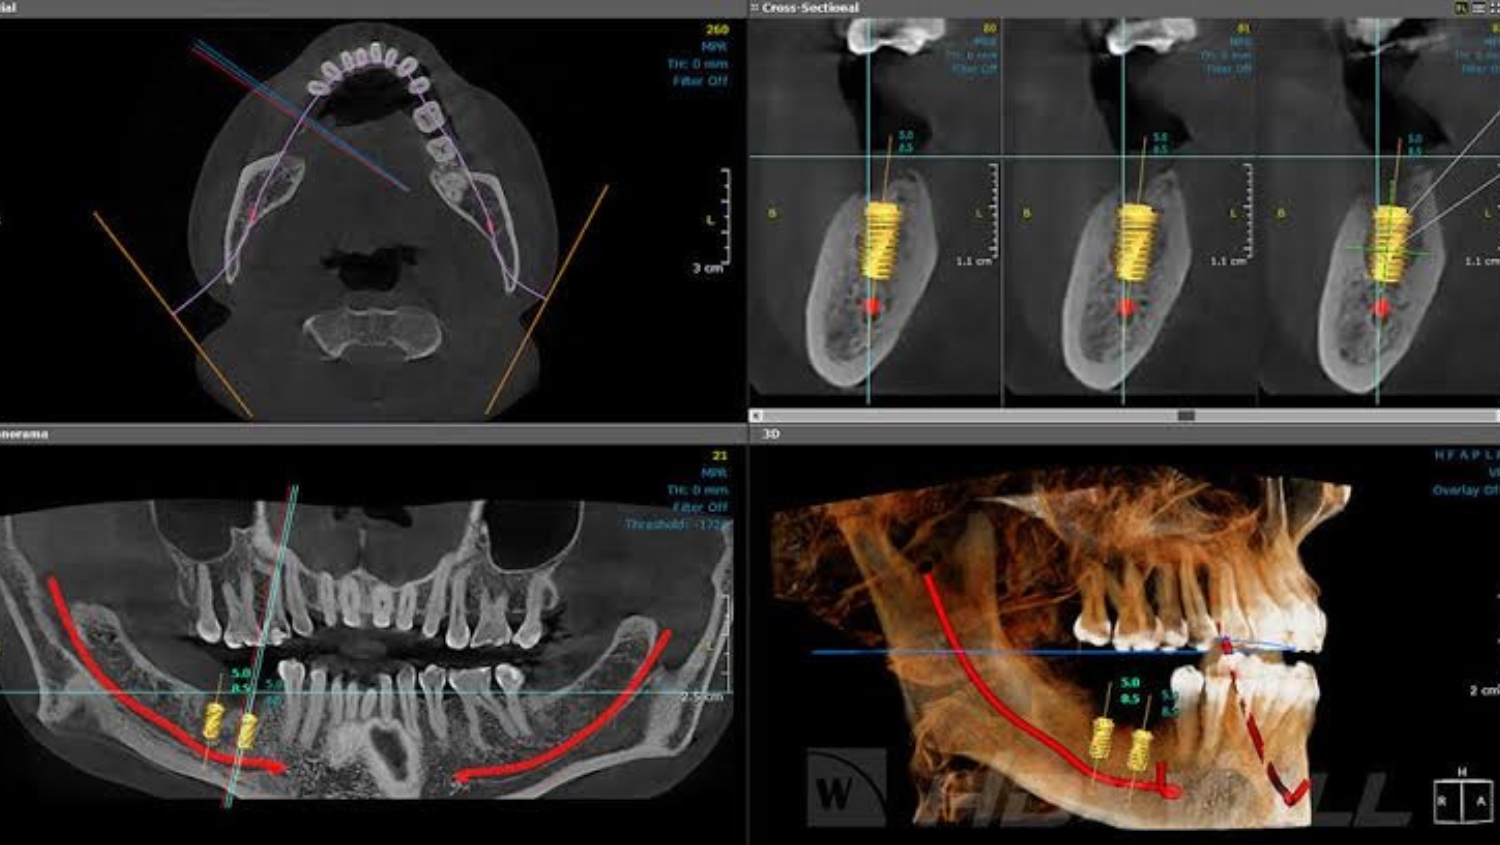

Fase de Planificación

01

Esta primera fase es de suma importancia para el éxito del tratamiento, durante este proceso se realizará un escaneo 3D, set de fotografías intraorales y extraorales, tomografía cone beam, registro de la mordida, y se confeccionará una guía tomografía y quirúrgica personalizada.

Con los resultados obtenidos de la tomografía tendremos información clara sobre la estructura ósea existente, podremos evaluar las medidas del hueso en profundidad y ancho además de su densidad. Con esto elegiremos el tipo de implante más adecuado.

De ser escaso e insuficiente el hueso se realizará un injerto óseo previamente a la colocación de los implantes. Todo esto será explicado y conversado con el paciente previamente a la cirugía.